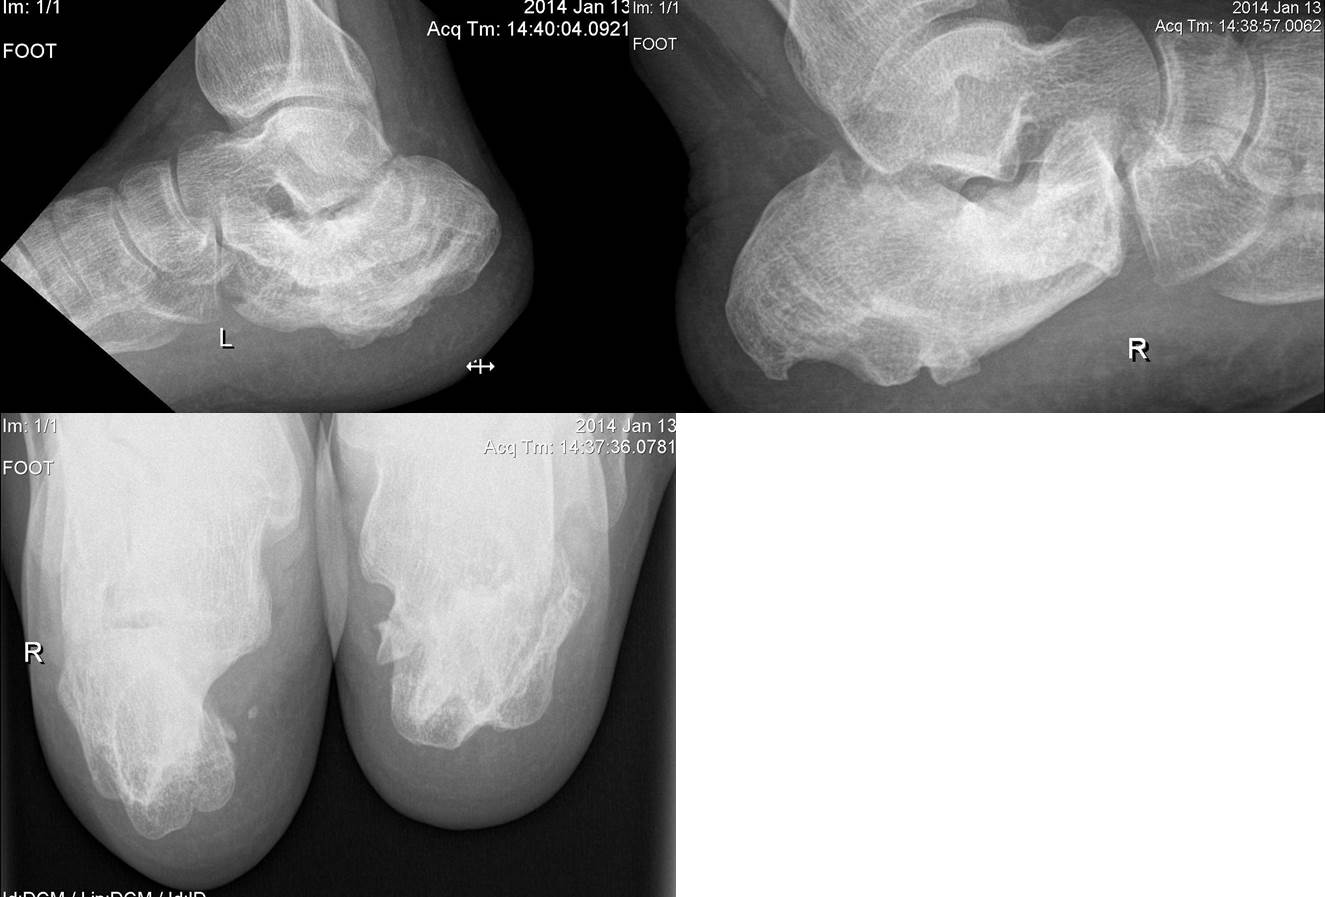

Деформация пяточных костей

Здравствуйте, уважаемые коллеги. У пациента 35 лет посттравматическая деформация обеих пяточных костей трехлетней давности.

Лечился консервативно в одном из сибирских городов нашей страны. Сейчас беспокоит боль, больше в правой стопе, после нагрузки и в покое. Хромает, дополнительной опорой не пользуется. Пациент военнослужащий и желает продолжить службу, а при такой деформации вряд ли он пройдет ВВК. Как служил до этого - не знаю... Помогите, пожалуйста, определиться с дальнейшей тактикой. Есть ли методы коррекции такой деформации? Заранее спасибо.

В значительной степени боль у данного пациента должна быть обусловлена состоянием подтаранных суставов. По снимку худшая ситуация на левой стопе. И там, вполне вероятно, имеется фиброзный анкилоз, чем и объясняется меньшая выраженность болевого синдрома. Без артродеза подтаранного сустава здесь не обойтись. Лучше бы иметь и компьютерные томограммы. Теоретически, можно попробовать сделать диагностическую блокаду подтаранного сустава и посмотреть, какой будет реакция. Хотя, при такой деформации сложно расчитывать на адекватное распространение анестетика по полости сустава. Да и сомнений в необходимости подтаранного артродеза тут не должно быть.

У больного подтаранный артроз. Не исключены другие причины болей. Сама деформацтя после перелома пятки не болит. Если потвердится диагноз артроза я за артродез с одновременной остеотомией типа маллерба можно попробовать по дваеру, но с дополнительной корекцией. После этого он будет практически здоров, если нет других причин болей, обследование изотопов +CT+3D+поиск невролгии.